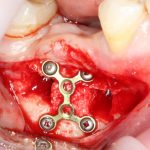

— минипластины. Их выпускается огромное количество. Мы используем, в основном, X- и Н-образные минипластины наименьших размеров — с ними легче работать, они легко адаптируются, но есть и минус — иногда гнутся под нагрузкой.

Мы особо не паримся с металлом, предпочитая ритм-энд-блюз или джаз, но если приходится, то нас вполне устраивает отечественный производитель «Коррозия металла» КОНМЕТ:

При горизонтальной остеотомии, на мой взгляд, удобнее использовать минипластины. Как я уже отмечал выше, в практике мы используем X- и H-образные минипластины под винты размером 0.9х4мм. Количество металла в разных условиях может быть разным — всё зависит от того, на каком этапе достигается полная неподвижность перемещенного костного фрагмента.